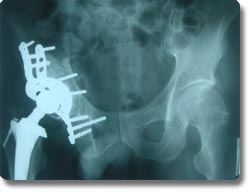

四肢大关节人工关节置换术

关节置换可以说是本世纪骨科手术最伟大的突破之一。目前它已应用於治疗肩关节、肘关节.腕关节、指间关节 、髋关节、膝关节及踝关节等疾患,但以全人工髋关节及膝关节置换最为普遍。对骨关节炎、股骨头无菌性坏死、老年性股骨颈骨折等疾病具有明显治疗效果,我科目前已开展各种置换手术800余例,疗效受到患者普遍肯定。